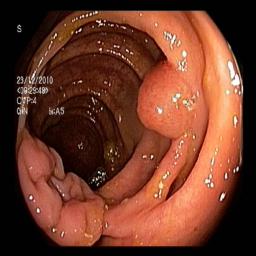

The performance metrics for Edgeconnect and AOTGAN on the validation data after fine-tuning the models, are shown in Table II. In addition to qualitative evaluation, Figure 3 provides example data from the different steps of the PolypConnect pipeline using the EdgeConnect model and the AOTGAN model. Due to obvious visual differences in the generated polyps between the models, we selected the EdgeConnect model as the main polyp inpainting model of the PolypConnect pipeline for further evaluation and qualitative assessment by domain experts.

Figure 3: Sample data used and generated in the different steps of PolypConnect pipeline. (a) - real polyp images, (b) - manually annotated polyp masks, (c) - randomly selected colon images used as input to the final step of PolypConnect, (d) - extracted edge images of row c. (e) - extracted edge images of polyp regions of row a using the masks of row b. (f) - combined edge images of row d and f. (g) - generated polyp on the images of row c using EdgeConnect. (h) - generated samples from AOTGAN.